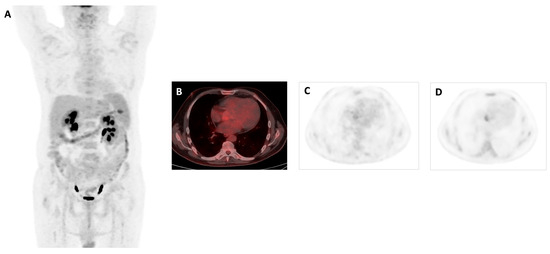

- Uptake suggestive of infection: intense elevation of 18F-FDG (hypermetabolism) of focal and/or heterogeneous type in relation to prosthetic material or cardiac lesions, identified in both corrected and uncorrected images. In the case of PVE, it was also required that the prostheses had been placed more than 3 months ago.

- Increased intensity in late acquisition compared to early acquisition was suggestive of infection.

- The sole appearance of increased focal or heterogeneous uptake in late acquisition was suggestive of infection.